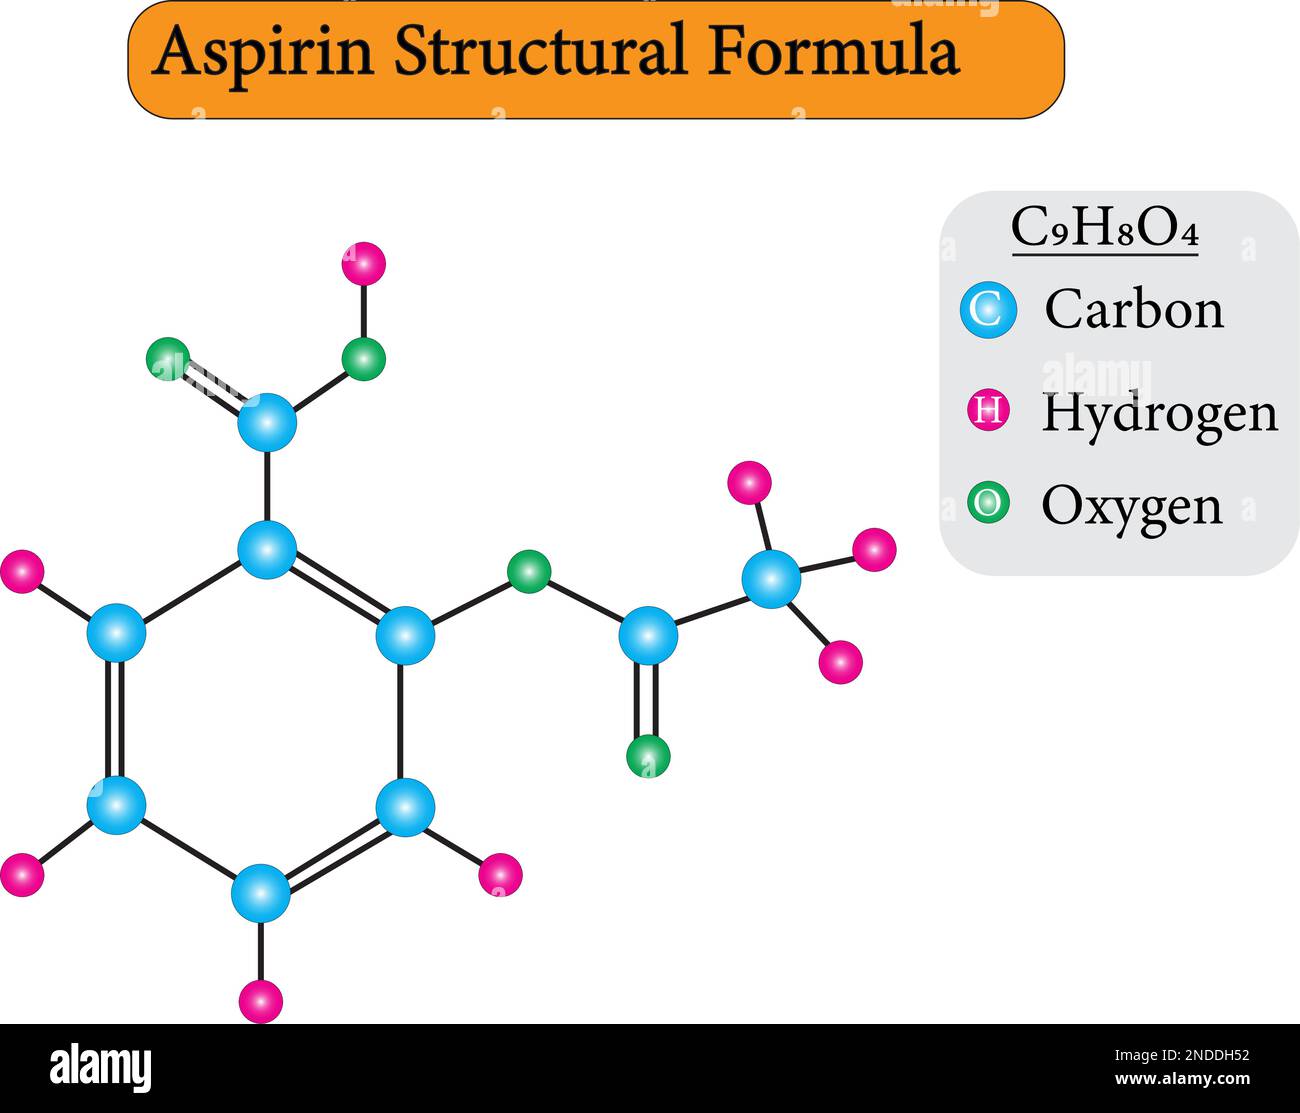

RF2NDDH52–Aspirin Formula is given and explained here along with its structure. To recall, aspirin is also known as acetylsalicylic acid (ASA) and used as a me